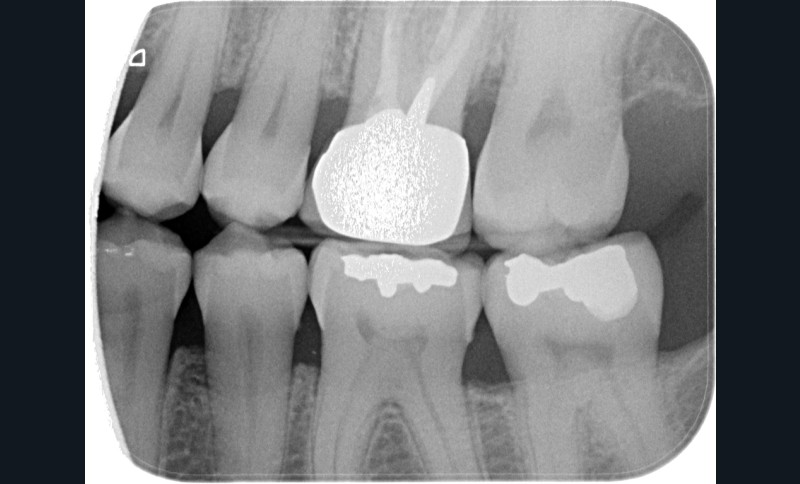

Aspect clinique et radiographique des lésions d’abrasion

Cliniquement, les lésions d’abrasion sont caractérisées par des facettes lisses, une absence de convexité et des bords à angles vifs. La flexibilité du ligament alvéolo-dentaire va entrainer un frottement au niveau des points de contact, qui peuvent se transformer en surfaces de contact (fig. 2c-d, 3 et 4b-c).

Radiographiquement, on observe une perte des cuspides et un aspect plan des faces occlusales (fig. 2a-b et 4a).